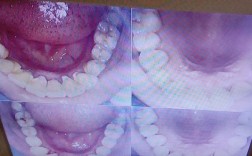

正畸诊疗的首要环节是全面、系统的评估,这是制定合理治疗方案的前提。病史采集需详细记录患者主诉、现病史(如牙齿排列异常、咬合问题的发展过程)、既往史(有无正畸治疗史、牙周治疗史、全身性疾病史)、家族史(有无类似错颌畸形遗传史)等,同时关注患者的治疗期望值和依从性。临床检查包括口外检查与口内检查:口外检查重点观察面部对称性、比例关系(如面高、面型)、唇闭合度、颞下颌关节区有无压痛、弹响及开口度;口内检查则需记录牙齿数目、形态、位置(如拥挤度、扭转、间隙)、牙弓形态与大小、咬合关系(如覆合、覆盖、中线偏斜、 Spee曲线深度)、牙周状况(牙龈指数、牙周袋深度、附着丧失)、口腔卫生情况及口腔黏膜健康状态。影像学检查是评估的重要辅助手段,常规拍摄全景片观察全口牙根形态、牙槽骨高度、恒牙胚发育情况;拍摄头颅侧位片进行X线头影测量分析,涵盖骨骼型(ANB角、SN-Mg角)、牙型(U1-SN角、L1-MP角)、软组织型(鼻唇角、唇突度)等指标;对于复杂病例(如骨性错颌、埋伏牙、颞下颌关节病变),需补充锥形束CT(CBCT)以获取三维影像信息,明确骨量、牙根位置及与重要解剖结构的关系,不同影像检查的适应症需严格把控,避免不必要的辐射暴露。